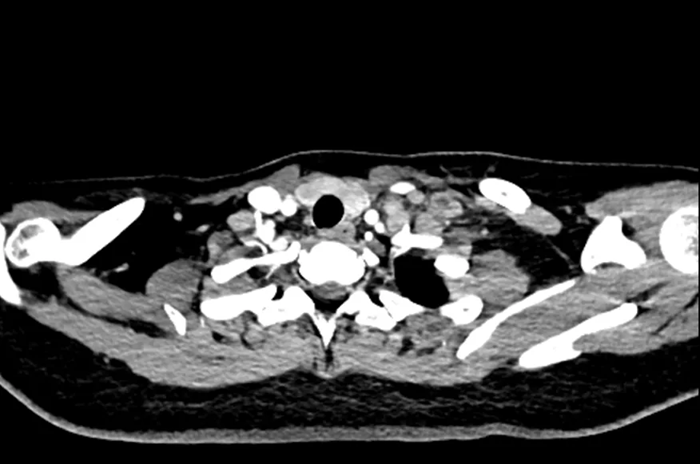

Hình ảnh chụp CT của nữ sinh 20 tuổi

Gần đây, một phụ nữ ngoài 20 tuổi đến khám tại Bệnh viện Nhân dân Đông Hoản (Quảng Đông, Trung Quốc) vì phát hiện khối u ở cổ trái trong khoảng một tuần.

Trước đó, cô cảm thấy vùng cổ đau nhẹ và sờ thấy một khối cứng kích thước gần bằng quả trứng gà. Khối u ấn vào có cảm giác đau nhưng không đỏ, không sưng. Điều đáng nói là cô không hề có triệu chứng tiêu hóa rõ ràng như đau bụng, đầy hơi hay sốt, ăn uống và đại tiện vẫn bình thường.

Sau khi nhập viện để kiểm tra toàn diện, bác sĩ tiến hành nội soi dạ dày và sinh thiết hạch cổ . Kết quả giải phẫu bệnh cho thấy bệnh nhân mắc ung thư biểu mô tuyến kém biệt hóa , trong đó có thành phần ung thư tế bào nhẫn - một dạng ung thư dạ dày ác tính cao.

Chụp CT cho thấy khối u đã di căn toàn thân , không còn chỉ định phẫu thuật. Các bác sĩ chỉ có thể đề nghị điều trị bằng hóa trị, xạ trị hoặc liệu pháp miễn dịch nhằm kiểm soát bệnh.